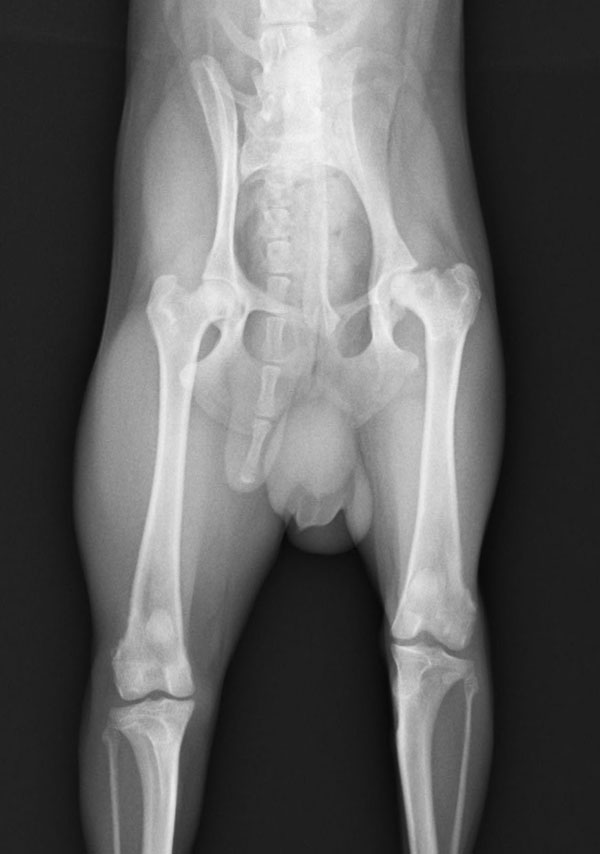

5~6歳以上の去勢手術をしていないオス犬に多い病気ですが、メス犬や去勢した犬に起こることもあります。お尻の筋肉が萎縮した結果、筋肉の隙間から直腸や膀胱が皮膚の下にとびでてしまいます。これにより便が出にくくなったり膀胱炎になったりします。手術をすることで機能回復および今後の致死的な状況を回避することができます。当院では去勢手術→結腸固定→前立腺固定→骨盤隔膜構成筋の縫縮→内閉鎖筋フラップ→浅臀筋フラップの順で通常腹側・臀部左右両側同時に行います。また老化以外に、筋肉が萎縮する原因があったり、腹圧がかかる原因があったりする場合も多いので、再発防止のためそれらの診断・治療も重要です。今回のワンちゃんも無事手術も終わり元気に退院しました。よかったね。